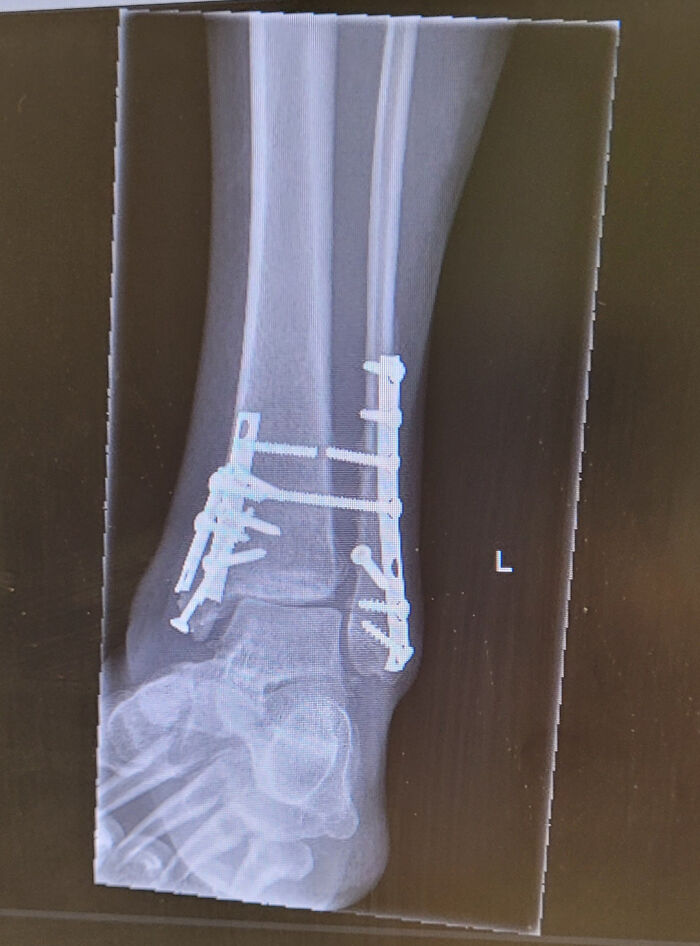

Ankle Injury, 15 Week Update

The news wasn't the best. The doctor said the bones are healing fine, but they seem to be moving apart. You can see the top syndesmotic screw is already broken- however, he thinks my issue is the ligament(s). So now I wait for a CT scan.